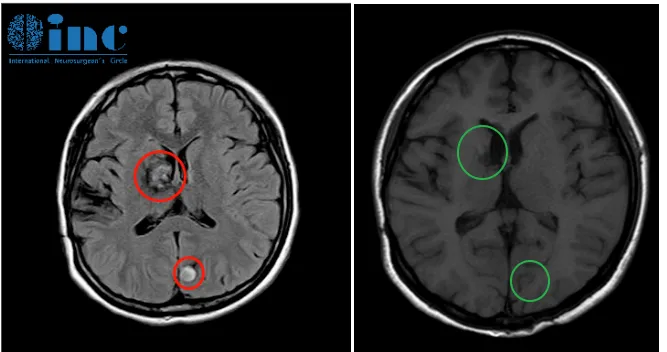

巴教授术后影像对比

18岁的多发脑海绵状血管瘤患者嘉佳,4岁时在国内进行了第一次手术,切除了两侧的海绵状血管瘤。多年来反复出血,再次手术还会复发吗?

“完全切除后,复发的可能性极低,但在海绵状血管瘤中,答案不是100%,因为这是一种遗传性疾病。由于基因的驱动,在另一个地方,现在看不见的新病变可能会在后期发生(这不是必然的,但有可能)。”

巴教授术后1年随访影像对比